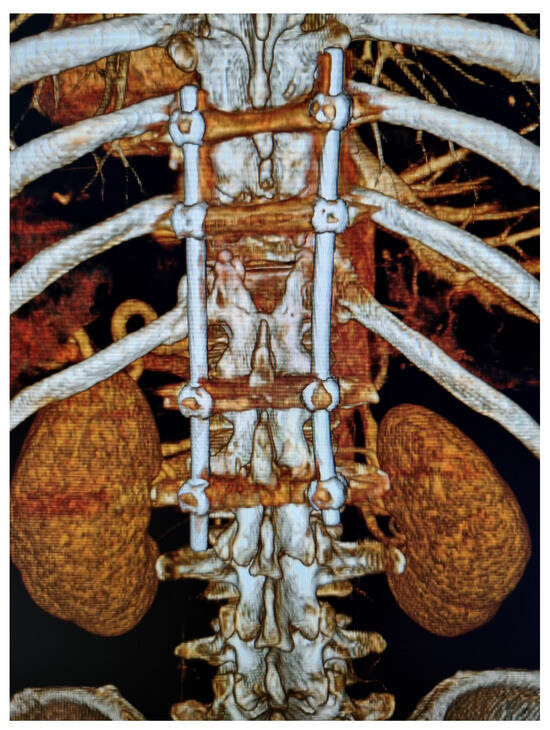

Integrated Clinical Workflow for Preoperative Planning and Resection of Giant Iliofemoral Heterotopic Ossification Using Three-Dimensional Technologies

Background/Objectives: Neurogenic heterotopic ossification (HO) is an abnormal formation of lamellar bone in soft tissues, frequently developing near major joints in patients with spinal cord injury. While imaging provides valuable diagnostic insights, large and anatomically complex HO often requires advanced preoperative planning to minimize surgical risks. This study presents the development and clinical application of a structured six-stage workflow integrating three-dimensional (3D) technologies for the preoperative planning and surgical resection of giant iliofemoral HO. Materials and Methods: A workflow was developed comprising: (1) 3D imaging acquisition, (2) creation of a virtual model, (3) production of a life-size physical model, (4) preoperative simulation, (5) surgical resection, and (6) postoperative imaging validation. The workflow was applied to a 50-year-old male with paraplegia after a T12 fracture who developed a 26 cm iliofemoral bony bridge, confirmed by computed tomography and 3D reconstruction. Results: The physical model provided a precise anatomical reference, enabling detailed surgical rehearsal and safe planning of neurovascular dissection. Resection was performed using combined orthopedic and vascular techniques. The hip joint was preserved, and postoperative rehabilitation achieved improved range of motion and patient handling without major complications. Conclusions: This structured 3D-assisted workflow enhanced anatomical understanding and surgical precision in this complex case. The framework is applicable to other extensive ossifications with intricate anatomical relationships and warrants further evaluation in larger series. Full article

Show Figures

Figure 1